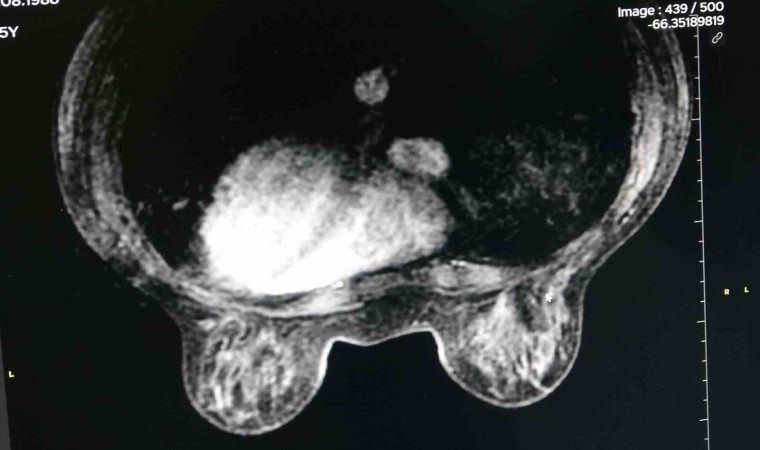

Dünyada, önemli bir halk sağlığı sorunu olan meme kanseri, kadınlarda en sık rastlanan kanser türü arasında ilk sırada yerini alıyor. Diyarbakır Gazi Yaşargil Eğitim Araştırma Hastanesinde Meme Radyolojisi Uzmanı Dr. Derya Deniz Altıntaş, hastanedeki tanısal meme biriminde özellikle meme kanserinde erken tanının mamografide izlenen mikrokalsifikasyonlar ile konulduğunu belirtti. Altıntaş, “Hastanemizdeki tanısal meme biriminde özellikle memesinde şüpheli bulunan hastaları memesinde şüphe olan hasta grubunu kabul ediyoruz. Bu süreçte hastaların tanı, tedavi yönetimi ve takip kısmını birkaç birimin işbirliği içerisinde olduğu multidisipliner yaklaşımla yapmayı planlıyoruz. Birimimiz özellikle meme kanserinde erken tanıda çok önemli olan mamografide gördüğümüz mikrokalsifikasyonlara yönelik mamografi eşliğinde telle işaretlemenin yapılan bölgede tek hizmet veren birim olma özelliğine sahiptir. Bununla birlikte özellikle hastaların tanı tedavi ve takip süreci bizim için çok önemlidir. Hasta şüphe halinde ve çözüm aşamasında nereye gideceğini bilsin istiyoruz. Tedavi sürecinde güvenli bir şekilde tedavisinin tüm süreçlerini bilsin istiyoruz. Dolayısıyla bir hasta şüpheli bir durum varlığında hiç çekinmeden birimimize başvurabilirler” dedi.